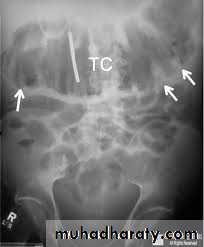

Toxic megacolon

Toxic megacolon (TM) is complication that can be seen in both types of inflammatory bowel disease, in infectious colitis, as well as in some other types of colitisRadiographic features

The colon (typically transverse colon) becomes dilated to at least 6cm (usually greater).There is additional loss of haustral markings, with pseudopolyps often extending into the lumen.

Thumbprinting from mucosal edema may be present.